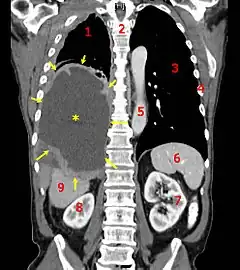

| A coronal CT scan showing a malignant mesothelioma Legend: → tumor ←, ✱ central pleural effusion, 1 & 3 lungs, 2 spine, 4 ribs, 5 aorta, 6 spleen, 7 & 8 kidneys, 9 liver | |